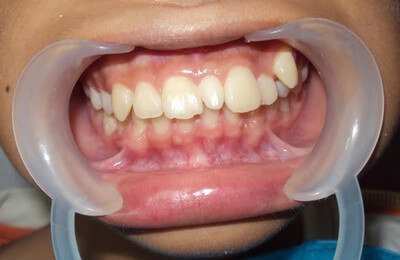

Supplemental supernumerary teeth are the most common in primary dentition. They almost always erupt. They appear along with the continuity of the alveolar line. The most common location is lateral incisors.

Picture 9: Supplemental Supernumerary Tooth

Image Source: askanorthodontist.com